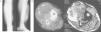

A 64-year-old patient with a history of a tibia fracture 12 years before, which was treated with a long-leg plaster. In the anamnesis carried out, the patient remembered the presence of repeated haematomas on the leg, which required repeated punctures to clear. As a consequence of the whole process, there was a residual equinus, which required a plasty of the posterior tibia. A few years before coming to our surgery, he noticed a painless hard tumour, which was progressively growing. Due to its size, he was sent to our centre with a suspected malignant tumour or myositis ossificans. After a radiographic study, the MRI established the diagnosis of calcific myonecrosis (Fig. 2). Given that he was asymptomatic and because of the possible complications from surgical treatment, we decided that, with the patient's consent, we should monitor his progress. Three years later, a small trauma produced a wound through which haematic and slough drained. It was operated on with a surgical debridement of the lesion and haematic material, necrotic muscle and multiple calcifications were removed. The wound was finally closed with drains. Two weeks later there was a dehiscence of the surgical wound with the release of a purulent liquid that gave positive cultures to Staphylococcus aureus and enterobacter, forcing new debridement and specific antibiotic treatment. The wound later needed new debridement, applying growth factors and VAC therapy so that it could close. Despite all the treatments performed, there is still a chronic fistula, which is well tolerated by the patient.

AP X-ray of the leg (right) and MRI coronal slices in T1-weighted sequences (central) and T2 (left), identifying typical calcifications, together with the soft tissue component (which can be better seen in the MRI) and which has a complex cystic appearance. We can also see the consolidated fracture of the proximal tibial metaphysis.